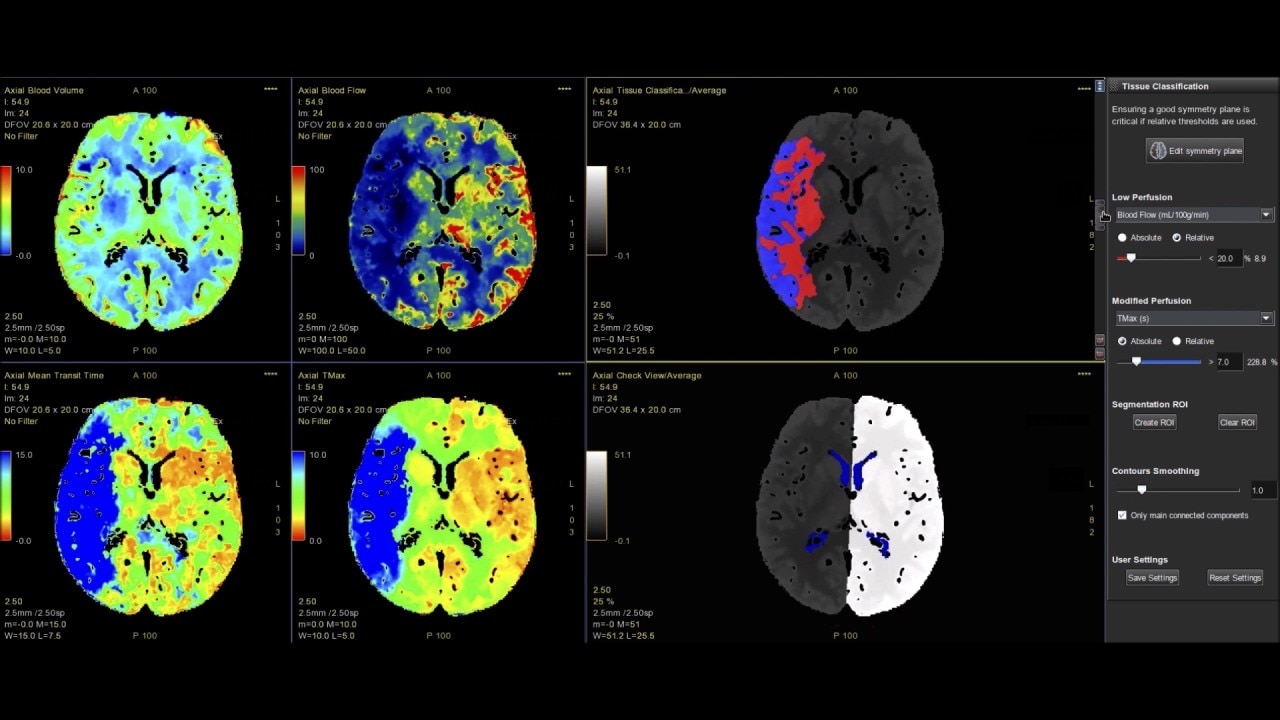

Brain perfusion

Easy-to-use automated workflow for CT stroke and tumor angiogenesis evaluation

Brain stroke protocol

• Image Registration to minimize the effects of patient movement

• Bone Removal to remove the cranium automatically from the dataset

• Deep Learning brain ventricle segmentation to prevent ventricular matter inclusion in quantitative results and improve visual inspection of the maps

• Automated selection of arterial input and venous output. Both can be easily adjusted if needed.

• Automated generation of all functional maps: Blood Flow, Blood Volume, Mean Transit Time, and Transit Time to IRF Peak (Tmax)

• Automatically define the symmetry plane to be used for mirroring ROIs and relative thresholds

• Tissue Classification enables the visualization of regions that are segmented from absolute or relative values, customizable thresholds and user selectable input maps

• Mismatch volume and ratio are calculated from the modified perfusion volume and low perfusion volume ROIs